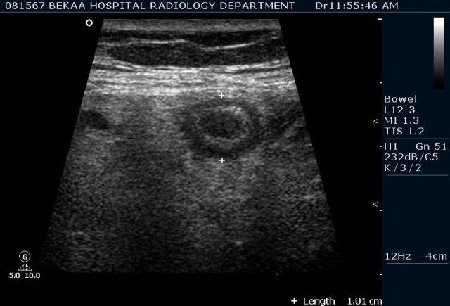

Диагностика острого аппендицита по УЗИ: очень актуальная тема; УЗ аппараты практически есть во всех клиниках; метод доступный и не сложный; главное владеть правильной техникой. Не буду загружать лишней теорией и разными ссылками; поделюсь практическим опытом. У меня линейный датчик 3-12 мегагерц с плавающей частотой; аппарат Филипс HD 11, всегда включаю соно-КТ (9800 цифровых каналов) и гармонику когда смотрю кишечник. Нормальный аппендикс видеть можно; но вопрос зачем??? Как правило, если при наличии достаточного опыта аппендикс не виден; значит скорей всего аппендицита нет. Когда "идешь" на аппендицит то главное по началу набраться терпения и......хорошая компрессия! По началу надо минут 10-15; потом когда появится достаточный опыт; за 2-5 минут можно справится и получить отличную визуализацию. Мочевой пузырь лучше опорожнить; часто он приподнимают тонкий кишечник и может закрыть "окно" через которое будет видно апендикс. Сначала находим слепую кишку потом находим илео-цекальное соединение;

после начинаем производить хорошую компрессию датчиком попрося пациента сообщить в какой точке боль наиболее выражена; медленными движениями датчика сканируем область наибольших болевых ощущений и как правило находим утолщенный отросток. Лучше начинать с поперечной визуализации и идти к верхушке аппендикса что бы убедится что это аппендикс и он заканчивается, а не тонкая кишка (которая если и закончится то только переходя в слепую); потом надо аккуратно развернуть продольно датчик и посмотреть от верхушки аппендикса к слепой. Норма диаметра: 3-4 мм; 5-6 мм под вопросом (клиника решает; но я в катаральный аппендицит не верю); 7-8 мм и больше, не компремируемый (фиксированный отросток)-острый аппендицит! Помимо наличие утолщенного аппендикса; признака "бычьего глаза" (bull-eye sign) при поперечном сканировании; надо обращать внимание на присуствие аппендоколитов в просвете; деструкцию стенки и свободной жидкости в зоне интереса.